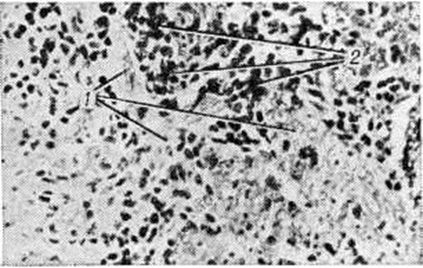

Макроскопически Лимфоэпителиома имеет форму узла или крупнобугристого образования плотноэластической консистенции покрытого первоначально неизменённой слизистой оболочкой, бледно-серого цвета на разрезе. Микроскопически Лимфоэпителиома построена из крупных пластинчатых клеток, лежащих разрозненно или образующих компактные гнезда и рыхло связанные тяжи (рисунок, 1). Опухолевые клетки имеют различную форму, контуры их неотчётливы; цитоплазма бледная, иногда отростчатая; ядра крупные, светлые, обычно округлой или овальной формы, с фуксинофильными ядрышками. В ткани Лимфоэпителиома иногда встречаются очаги плоскоклеточной дифференциации вплоть до ороговения отдельных клеток и образования так называемый раковых жемчужин. Строма опухоли состоит из нежно-волокнистой соединительной ткани, инфильтрированной лимфоидными клетками (рисунок, 2) и пронизанной многочисленными капиллярами. Выделяют так называемый тип Шминке, характеризующийся ретикулярным расположением эпителиальных и обилием лимфоидных клеток, и тип Рего с компактным размещением эпителиальных клеток и небольшим количеством лимфоцитов в виде отдельных очагов. Клинические, течение Лимфоэпителиома обусловлено инфильтративным характером роста опухоли, склонностью к раннему метастазированию в глубокие лимфатических, узлы шеи и быстрой генерализацией процесса. Особенности клинические, симптоматики зависят от локализации и распространённости Лимфоэпителиома (например, начальный симптом Лимфоэпителиома в носовой части глотки — затруднённое носовое дыхание; при поражении трубной миндалины — понижение слуха; при Лимфоэпителиома задней поверхности мягкого неба — затруднённое глотание и изменение тембра голоса). С помощью обычной задней риноскопии или фиброриноскопии чаще на боковой стенке носовой части глотки или в её своде определяется крупнобугристое образование плотноэластической консистенции (в отличие от мягких аденоидных разрастаний). По мере роста опухоль выпячивает мягкое небо, может распространяться в полость носа, околоносовые пазухи и глазницу. Иногда Лимфоэпителиома прорастает кости основания черепа и инфильтрирует среднюю черепную ямку, поражая при этом многие черепные нервы.